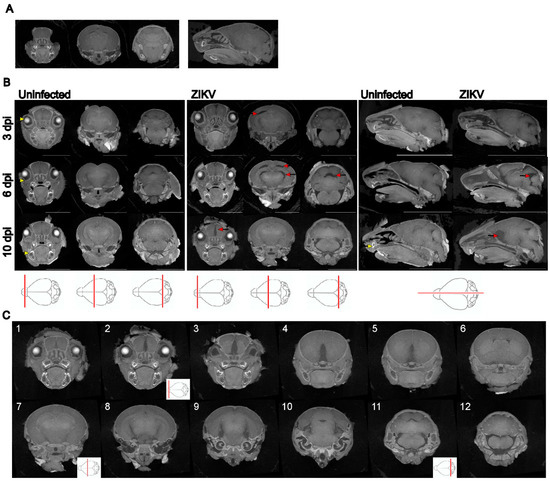

| Mouse ID | Reviewer 1 | Reviewer 2 | Reviewer 3 | Reviewer 4 |

|---|---|---|---|---|

| 1 | No pathological findings were noted | No pathological findings were noted | No pathological findings were noted | No pathological findings were noted |

| UI | UI | UI | UI | |

| 2 | Major gap at the rear of the brain | Asymmetrical gaps at the level of the hippocampus/thalamus | Asymmetrical, apparent volume loss in the hippocampus | Asymmetrical, increased space between the hippocampal region and thalamus and towards the hindbrain |

| ZIKV | ZIKV | ZIKV | ZIKV | |

| 3 | No pathological findings were noted | Some gaps, but no asymmetrical volume loss | No pathological findings were noted | Slight gaps between the hippocampal region and thalamus |

| probably UI | UI | UI | probably UI | |

| 4 | Multiple asymmetrical gaps penetrating across the midbrain | Clear asymmetrical gaps between structures, with the majority of abnormalities around the thalamus and hippocampus, continuing through the posterior brain | Very clear asymmetrical abnormalities, particularly at the level of the posterior hippocampus, and continuing more posteriorly | Gaps between hippocampus and cortex (right) and thalamus (left); Gap (right) appears to go through the majority of the brain |

| 5 | Maybe minor anomalies; | Asymmetrical gaps between the hippocampus and thalamus | Abnormality in the region anterior to nuc accumbens and at the level of striatum (less defined); Clear asymmetry at the level of the poster hippocampus; | Gap between the hippocampal region and the thalamus |

| UD | ZIKV | ZIKV | probably ZIKV | |

| 6 | Symmetrical gaps penetrating across images through the midbrain | Clear gaps at the hippocampus, continuing throughout the posterior brain | Very clear abnormalities, particularly at the level of the posterior hippocampus and extending posteriorly | Gap between the hippocampal region and thalamus on the left and right side, which runs through the majority of the brain |

| 7 | Maybe minor anomalies | Minor abnormalities | Some minor abnormality, which may be an imaging artifact or normal anatomical variation | Slight gap between the hippocampal region and thalamus; |

| UD | UI | UD | probably UI |